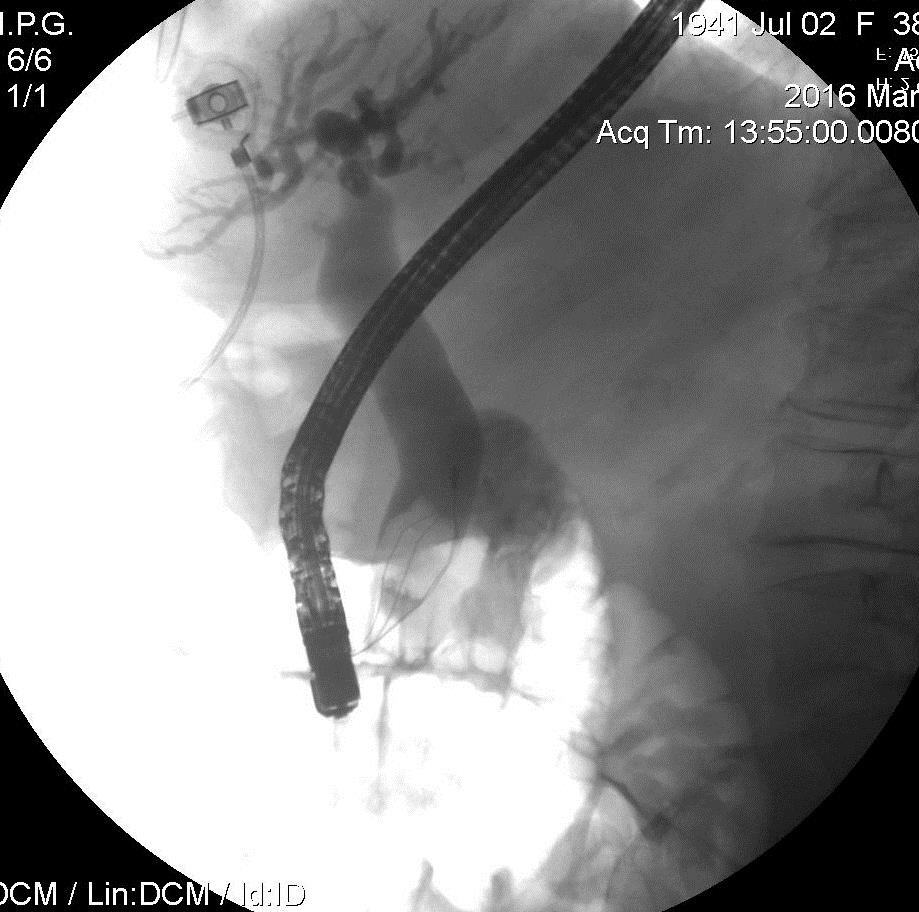

Конкремент в холедохе